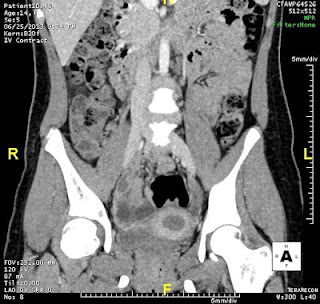

MÀNG TRINH BÍT

Bệnh nhân nữ 14 tuổi. Đau bụng hố chậu (P) 3 ngày, đau liên tục ngày càng tăng.

Tiền sử: Chưa có kinh lần nào.